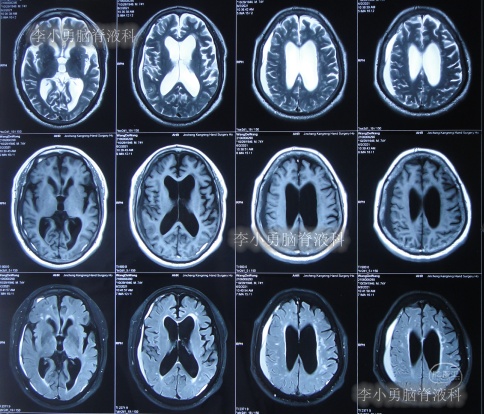

出院后再次转住入当地的第1家医院进行康复治疗,在该院康复治疗半年多的时间,不但没有持续好转,反而再次腰疼,走路不稳,且还出现了尿失禁的持续加重症状;治疗期间曾6次查头部影像(图-13、图-14、图-15、图-16、图-17)均示脑积水不断加重的趋势。

图-13:2021年5月22日头部核磁

图-14:2021年6月2日头部核磁

图-15:2021年7月24日头部核磁

图-16:2021年8月28日头部核磁

图-17:2021年9月28日头部CT